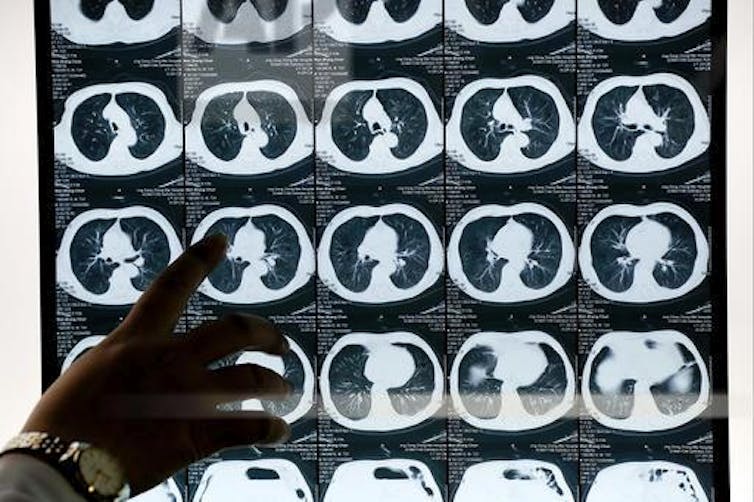

Smoking and lung cancer

So what is the evidence that smoking causes lung cancer?

In one type of epidemiological study, called case-control, people with cancer are compared to those without cancer for differences in personal habits, diet, environmental exposures and so on.

Beginning as early as 1939, it was found that men with lung cancer were much more likely to have been long-term smokers than men in the general population. Since then, many studies have also shown this.

This knowledge led to education and interventions that have in turn led to lower smoking rates among men and consequently lower lung cancer death rates in America. (Women started smoking later in history.)

Understanding how smoking causes lung cancer is not needed to effectively intervene and lower risk. The strategy is to discourage young people from starting to smoke, and help current smokers to quit.